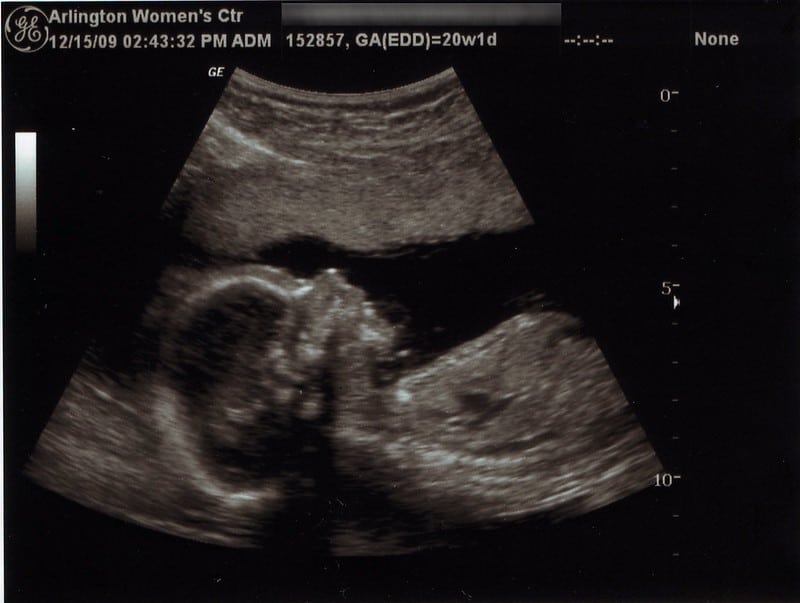

However, a baby’s ability to survive outside the womb is constantly changing thanks to advances in medicine. As a result, many states now have laws outlawing abortion starting at 20 to 22 weeks.

Abortion has been legal in all 50 states since 1973. However, that doesn’t mean the debate is settled regarding human rights. Indeed, since 1973, medicine has advanced dramatically and allowed glimpses into the womb. In turn, pro-life advocates have continued to challenge the narrative that the unborn child isn’t a baby.